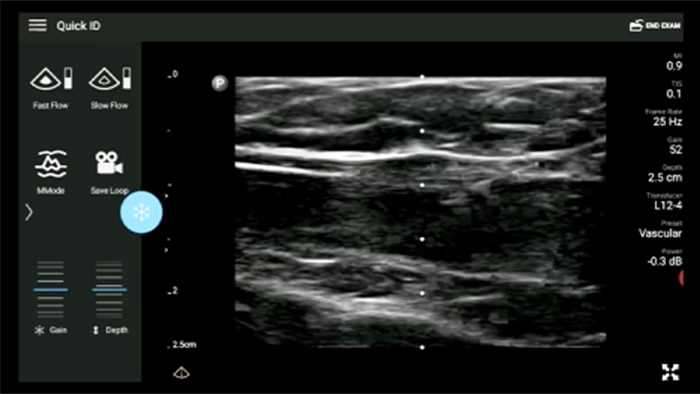

Exam results at your fingertips

Lumify makes it easy to store and access patient exam results and images right from your compatible Android or iOS device. You can even share those results with colleagues for better collaboration.

Lumify L12-4 broadband linear array transducer